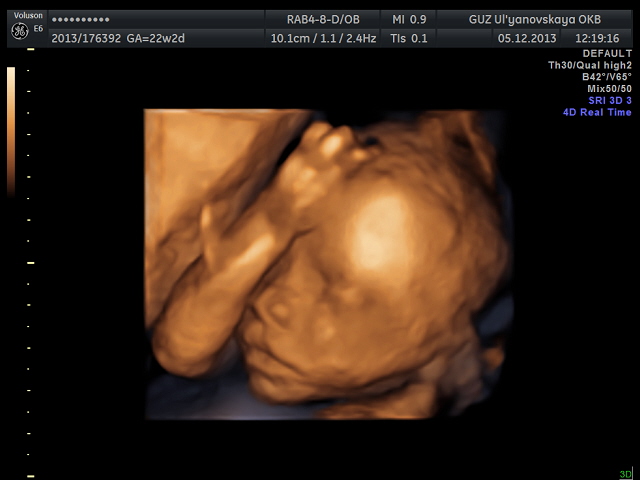

Сделали фото в 3D и записали даже на диск.

Ну вот наша Викулька. Свекровь говорит, что на младшего Никитку похожа будет.

Ну, и собственно, наша милая мордашка!!!!